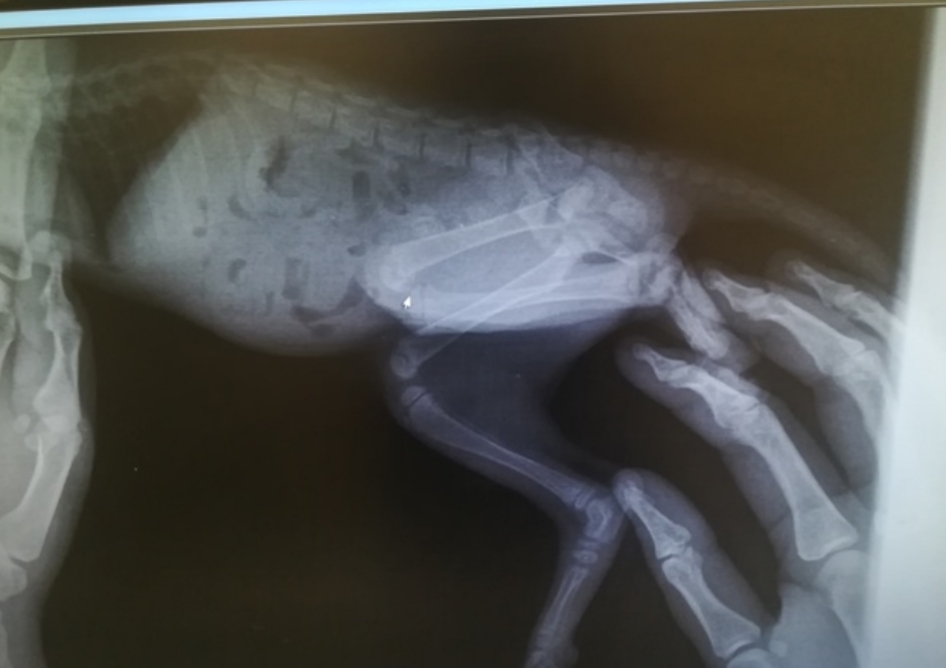

2 miesięczny kotek potrącony przez samochód. Kociak ciągnął tylne łapki, wykazywał silną bolesność podczas badania palpacyjnego. Po kroplówce maluch na cito zawieziony na RTG z podejrzeniem złamania w obrębie kości miednicy/ kręgosłupa. Na szczęście badanie nie wykazało złamań - wygląda na to, że maluszek miał dużo szczęścia. Co prawda w obrębie kości łonowej obraz rtg mocno zacieniony przez masy kałowe, więc jeśli niedowład łapek nie ustąpi, zrobimy kolejne rtg. Kotek ma silną krwawo - śluzową biegunkę. W związku z tym zrobiliśmy test na panleukopenię - na szczęście wyszedł ujemny. Maluch jest brudny, zabiedzony, strasznie głodny i spragniony... O dziwo bez świerzba i pcheł, nie wiemy jak z życiem wewnętrznym. Na dokładkę mamy też zaawansowany koci katar. Oczka są w bardzo złym stanie... ulicy maluch by nie przeżył! Teraz jest już bezpieczny w domu tymczasowym. Walczymy! Bardzo gorąco prosimy Was o wsparcie. Przed nami kolejne badania, długotrwałe leczenie kociego kataru, nie wiemy co jeszcze wyniknie po drodze. Kociak wymaga zbilansowanej diety i dokarmiania Convalescentem. Jeśli możecie dorzucić grosik - prosimy bardzo serdecznie.